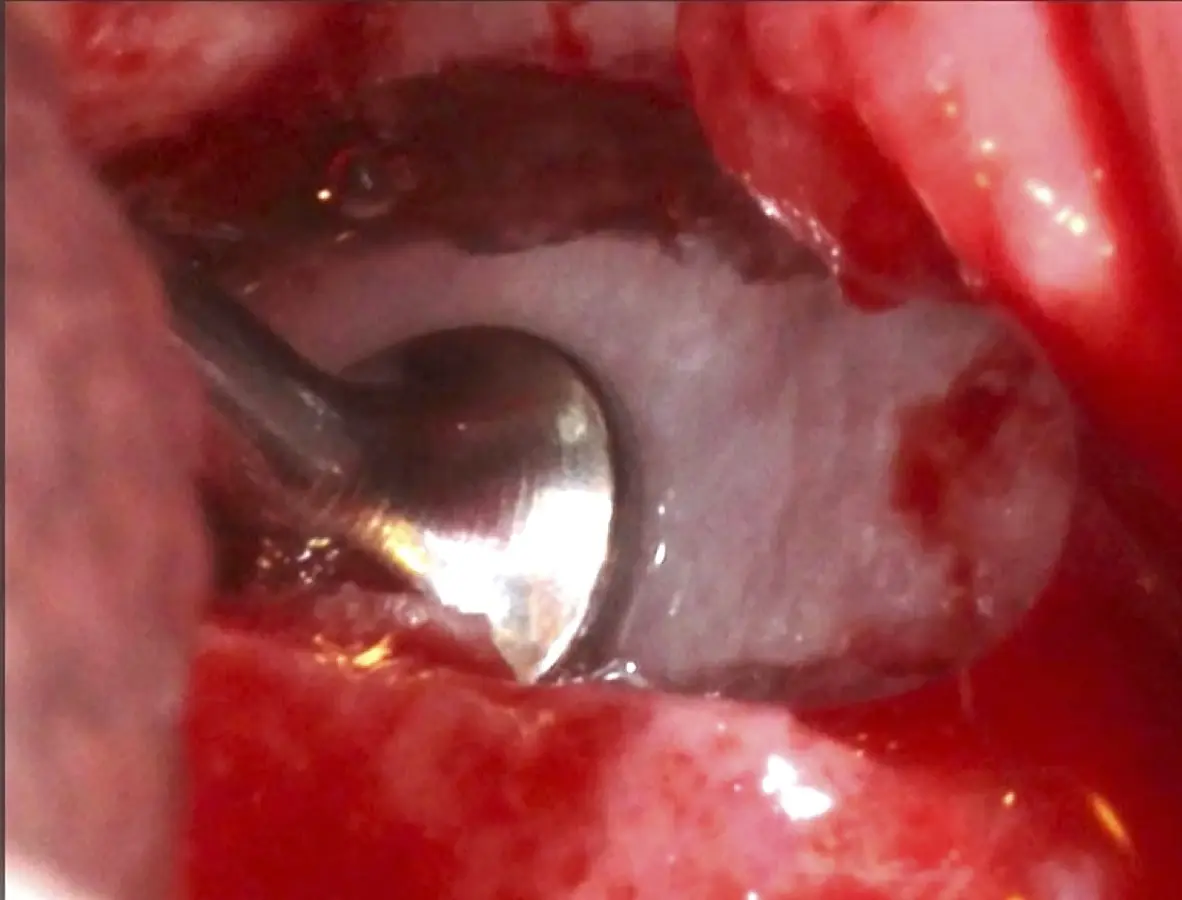

Se inicia la elevación de la membrana de Schneider con el inserto redondeado no cortante en forma de disco, empleando movimientos suaves. El levantamiento puede complementarse con elevadores convencionales, siguiendo la dirección mesiodistal. La fase de desprendimiento inicia con el piso y sigue hacia la pared mesial para terminar, y de ser necesario, hacia la pared posterior. Existen diversos insertos con angulaciones y longitudes para mayor accesibilidad16 (Figura 1).

Figura 1. Incisión y levantamiento de colgajo a espesor total.

Figura 17. Inicio del desprendimiento de la membrana de Schneider con el inserto de presión hidráulica.